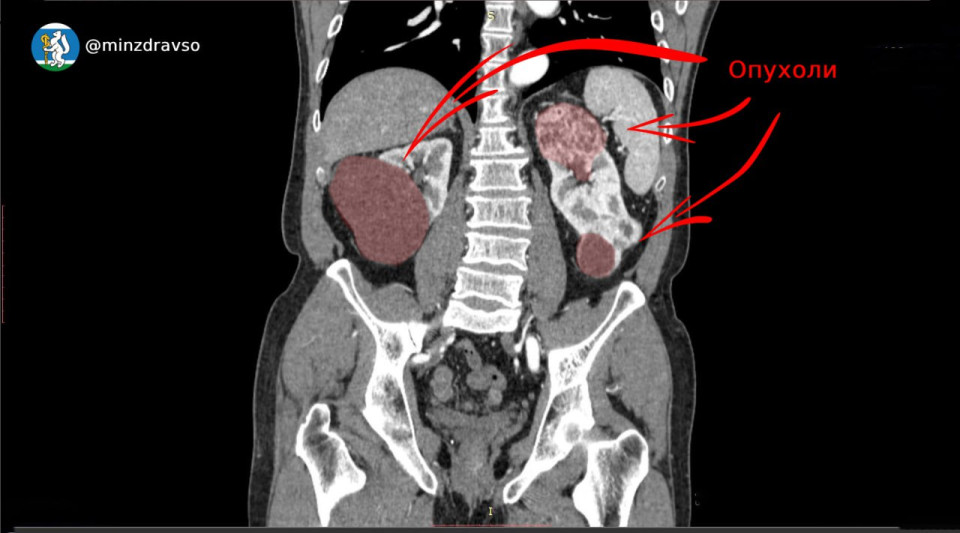

Такой синхронный рак, при котором на обеих почках есть объемные злокачественные новообразования, встречается лишь в 2-6% случаев. Болезнь у свердловчанина заподозрил врач во время планового медосмотра. Мужчину направили для детального обследования в Свердловский областной онкодиспансер.

Врачи выявили, что опухоль в правой почке имеет диаметр более 6 см и распространилась почти на 50% почечной ткани. Орган удалили, но вторая почка тоже была поражена опухолью. Образование удалили, сохранив 70% почечной ткани.

«Удаление образований общим размером 12 сантиметров выполнили успешно», — заключил минздрав.